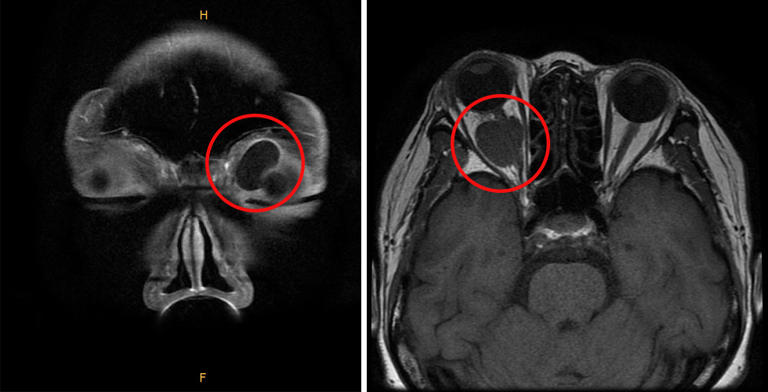

안와 종양 진단 방법은 환자의 얼굴을 관찰하고, 만져지는 덩어리가 있는지 확인하며, 덩어리에서 소리가 들리는지 확인하는 식으로 진행한다. 이후 안구돌출계를 이용해 눈에 안구 돌출이 발생했는지 확인한다. 이학적 검사상, 안와 사인이 명백하게 관찰되면 이후 CT, MRI 등 이미지 검사를 시행한다.

안와 양성 종양은 일반적으로 수술을 통해 제거한다. 하지만 발생 위치에 따라 합병증 발생 위험이 있어 신중하게 치료 방향을 결정해야 한다. 먼저 수술 전 CT 및 MRI 검사를 통해 종양의 크기, 위치, 성상을 정확하게 파악하고 분석한다. 안와 앞쪽에 위치한 종양은 상대적으로 쉽게 제거할 수 있다. 흉터 없이 제거하기 위해 쌍꺼풀 라인을 따라 절개하고 수술을 진행할 수도 있다.